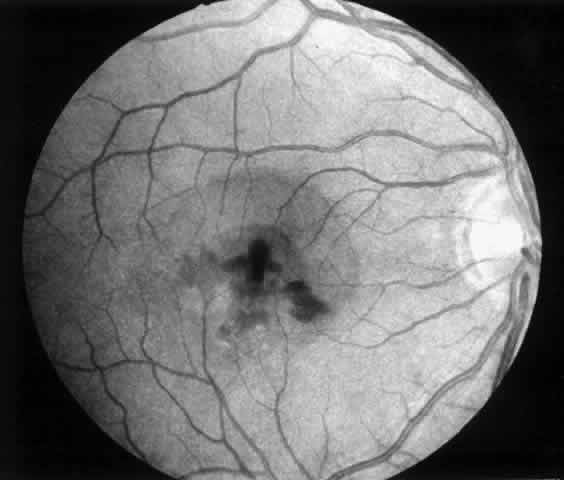

1. A 35-year-old patient with serpiginous choroidopathy developed a recurrent choroidal neovascular membrane extending into the fovea with a decrease in vision to 20/200 (6/60) (Fig. 7). Five months after surgery his visual acuity had improved to 20/25 (6/7.5) (Fig. 8).

Fig. 7. Preoperative fundus photograph of a 35-year-old patient with serpiginous choroidopathy and a recurrent subfoveal neovascular membrane (case 1). Visual acuity is 20/200 (6/60).